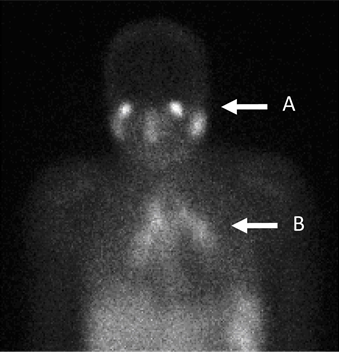

El galio tiende a concentrarse en zonas del cuerpo donde hay una rápida división celular. Esto se observa en las imágenes tomadas con la gammacámara. Cuando se observan grandes cantidades, puede ser un signo de infección, inflamación, lesión o posible cáncer. La imagen siguiente muestra cómo puede diagnosticarse la sarcoidosis mediante la gammagrafía con galio.

Imagen de escaneado de galio

Por A B Allard, J Buscombe, D P Kidd [CC BY-SA 4.0], a través de Wikimedia Commons

Diagnosticar afecciones inflamatorias como la fibrosis pulmonar o la sarcoidosis, como en la imagen anterior.